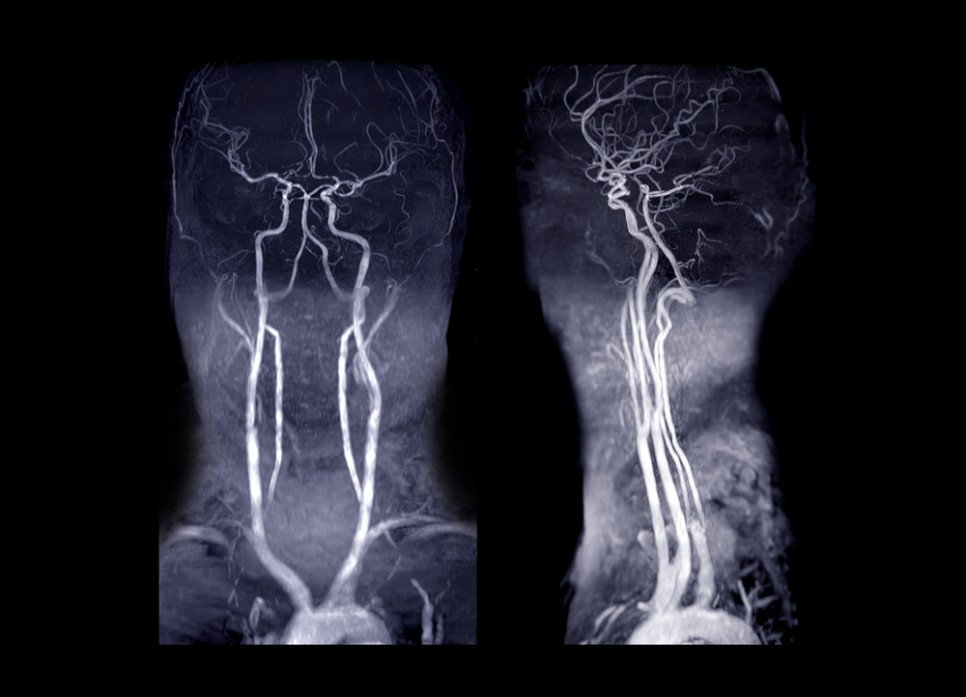

경동맥 협착증은 여러 진단 검사를 실시하고 심하지 않은 경우 약물 치료를 합니다. 경동맥협착증의 진단검사는 경동맥초음파검사, 컴퓨터단층촬영(CT), 자기공명영상(MRI), 경동맥혈관조영술 등을 시행합니다. 혈관조영술은 요즘에는 잘 쓰이지 않아요.

경동맥 초음파 검사(동맥 초음파 검사)는 목에 있는 동맥을 초음파로 조사하는 검사입니다. 이 경동맥 초음파 검사를 통해 경동맥의 동맥 경화 검사나 편두통의 원인 확인, 뇌 혈액의 순환 상태를 확인할 수 있습니다.

일반적으로 경동맥에 이상이 있는 경우 경동맥 초음파 검사를 실시하는데, 고지혈증이나 당뇨병, 편두통이 심하거나 치매가 의심되는 경우 이 검사를 통해 확인하도록 합니다.

경동맥 초음파 검사방법은 똑바로 누웠다가 고개를 옆으로 보면 초음파 검사기계를 목에 대고 혈관의 상태를 관찰하는 방법입니다. 통증이나 불편함 없이 10분 정도로 시간도 짧은 편입니다.

경동맥 초음파 검사 단식, 마취, 조영제 등은 필요 없다고 합니다.

경동맥 초음파는 병원에 따라 다르지만 5~10만원입니다. 경동맥 초음파 비용이 모두 다르기 때문에 검사를 실시하기 전에 병원에 문의 후 방문하시면 좋습니다.